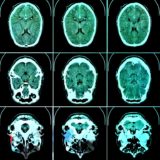

Ich werde beobachtet, mit

bildgebendem Verfahren;

die Psychologen haben

mein Neuronengewitter

auf dem Schirm, sagen,